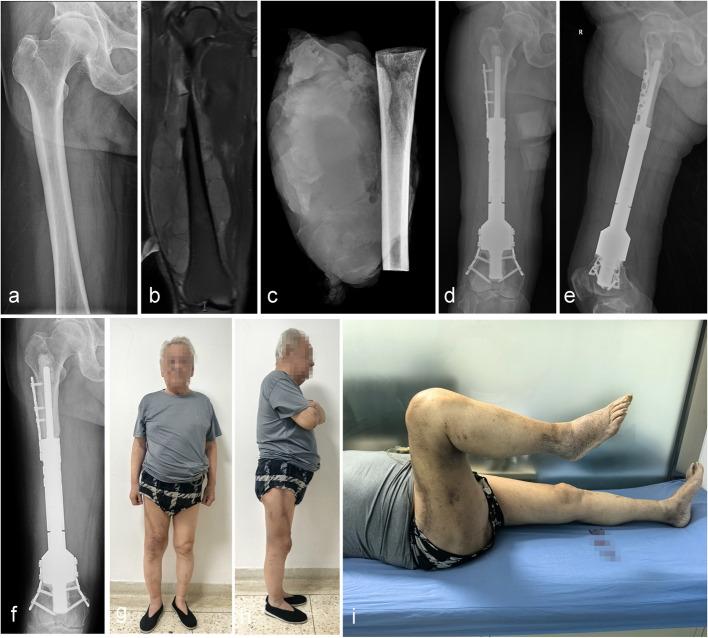

A retrospective analysis of 25 patients treated at two centers with wide resection for primary or metastatic bone tumors (femur, tibia, humerus) followed by reconstruction using ultra-short stem intercalary prostheses combined extracortical plates. Clinical outcomes were assessed using the Visual Analogue Scale (VAS) and Musculoskeletal Tumor Society (MSTS) score. Survival rates were calculated using the Kaplan-Meier method, and complications were classified according to the Henderson system.

The mean follow-up was 20.2 months (range, 3-101 months). The average length of the ultra-short stems was 41.3 ± 9.6 mm. Mean operative time was 164 ± 61.3 min, blood loss averaged 646.4 ± 375.5 ml and the mean defect size was 122 ± 52.1 mm. Postoperative VAS scores were significantly lower than preoperative levels (P < 0.05). The mean MSTS score was 24.2 ± 3.5 (range, 15-29). Kaplan-Meier analysis revealed prosthesis survival rates at 1, 2, 3, and 5 years of 91.7%, compared to patient survival rates of 74.5%, 52.7%, 52.7%, and 52.7%. Postoperative complications occurred in 12% of patients (3/25), including one case of aseptic loosening (ASL), and two patients required reoperation.

Ultra-short stem intercalary prostheses with extracortical plates provide a viable, effective option for reconstruction of short bone stumps after tumor resection, offering improved functional outcomes and acceptable prosthesis failure rates.